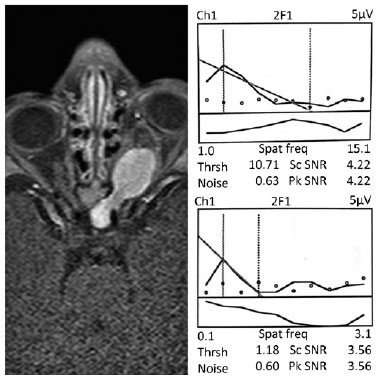

Grating acuity was estimated with an automated algorithm that performed a linear fit and extrapolation to zero amplitude for the final descending limb of the function relating each VEP amplitude (from the second harmonic) to a linear spatial frequency (Figure 1). A signal-to-noise ratio (SNR) at a peak of 3:1 was required and calculated as the ratio of the power at stimulus frequency to the mean power at frequencies ± 2 Hz, corresponding to a false alarm rate of 0.4 %, ensuring an adequate protection level when combined with the phase consistency criteria. In all cases, two thresholds (one for O1 and another for O2) were obtained. The final acuity score was calculated in logMAR (logarithm of the minimum angle of resolution) using the results in cycles per degree of visual angle of the better threshold channel with the highest SNR(13-16).

Visual impairment based on binocular GVAD (mean ± SD, 0.60 ± 0.36 logMAR; median, 0.56 logMAR) was detected in all children and was classified as mild in 10 children (40.0%), moderate in 8 children (32.0%), and severe in 7 children (28.0%). Increased IAD (>0.1 logMAR) was found in 16 children (64.0%). GVAD was comparable in boys and girls, and no correlation was found between age at tumor onset and GVAD. A representative SVEP response from the BSE and the WSE and the orbital magnetic resonance imaging (MRI) from a participant (subject S01) are shown in figure 1. The binocular GVAD scores, in logMAR units, of each participant in comparison with age norms from our laboratory are shown in figure 2. The distribution of all participants, considering the World Health Organization (WHO) classification of tumors, age (months) at SVEP evaluation, and GVAD scores (in logMAR units), is shown in figure 3.